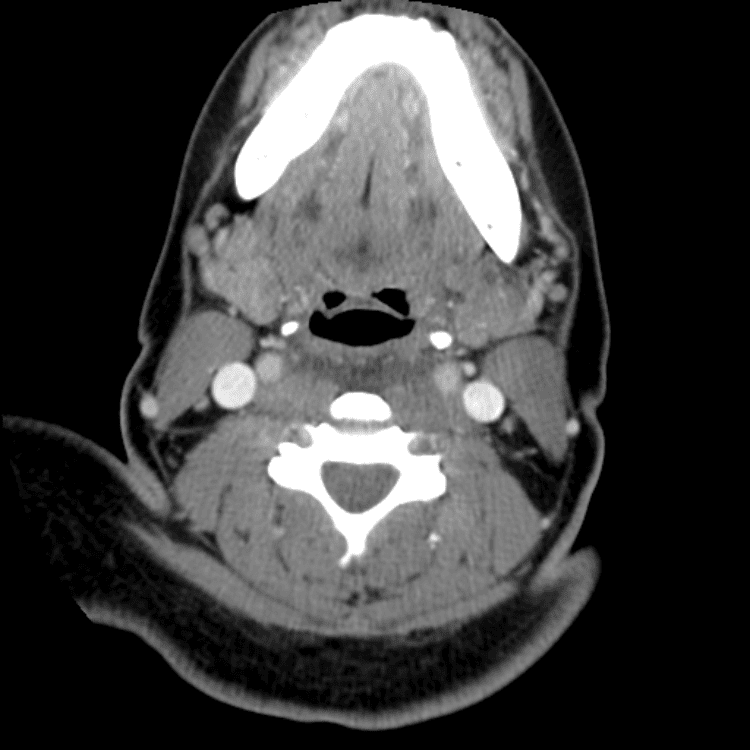

Head and Neck

Practice

Simulates call by including subtle or difficult cases and some normals.

27 cases